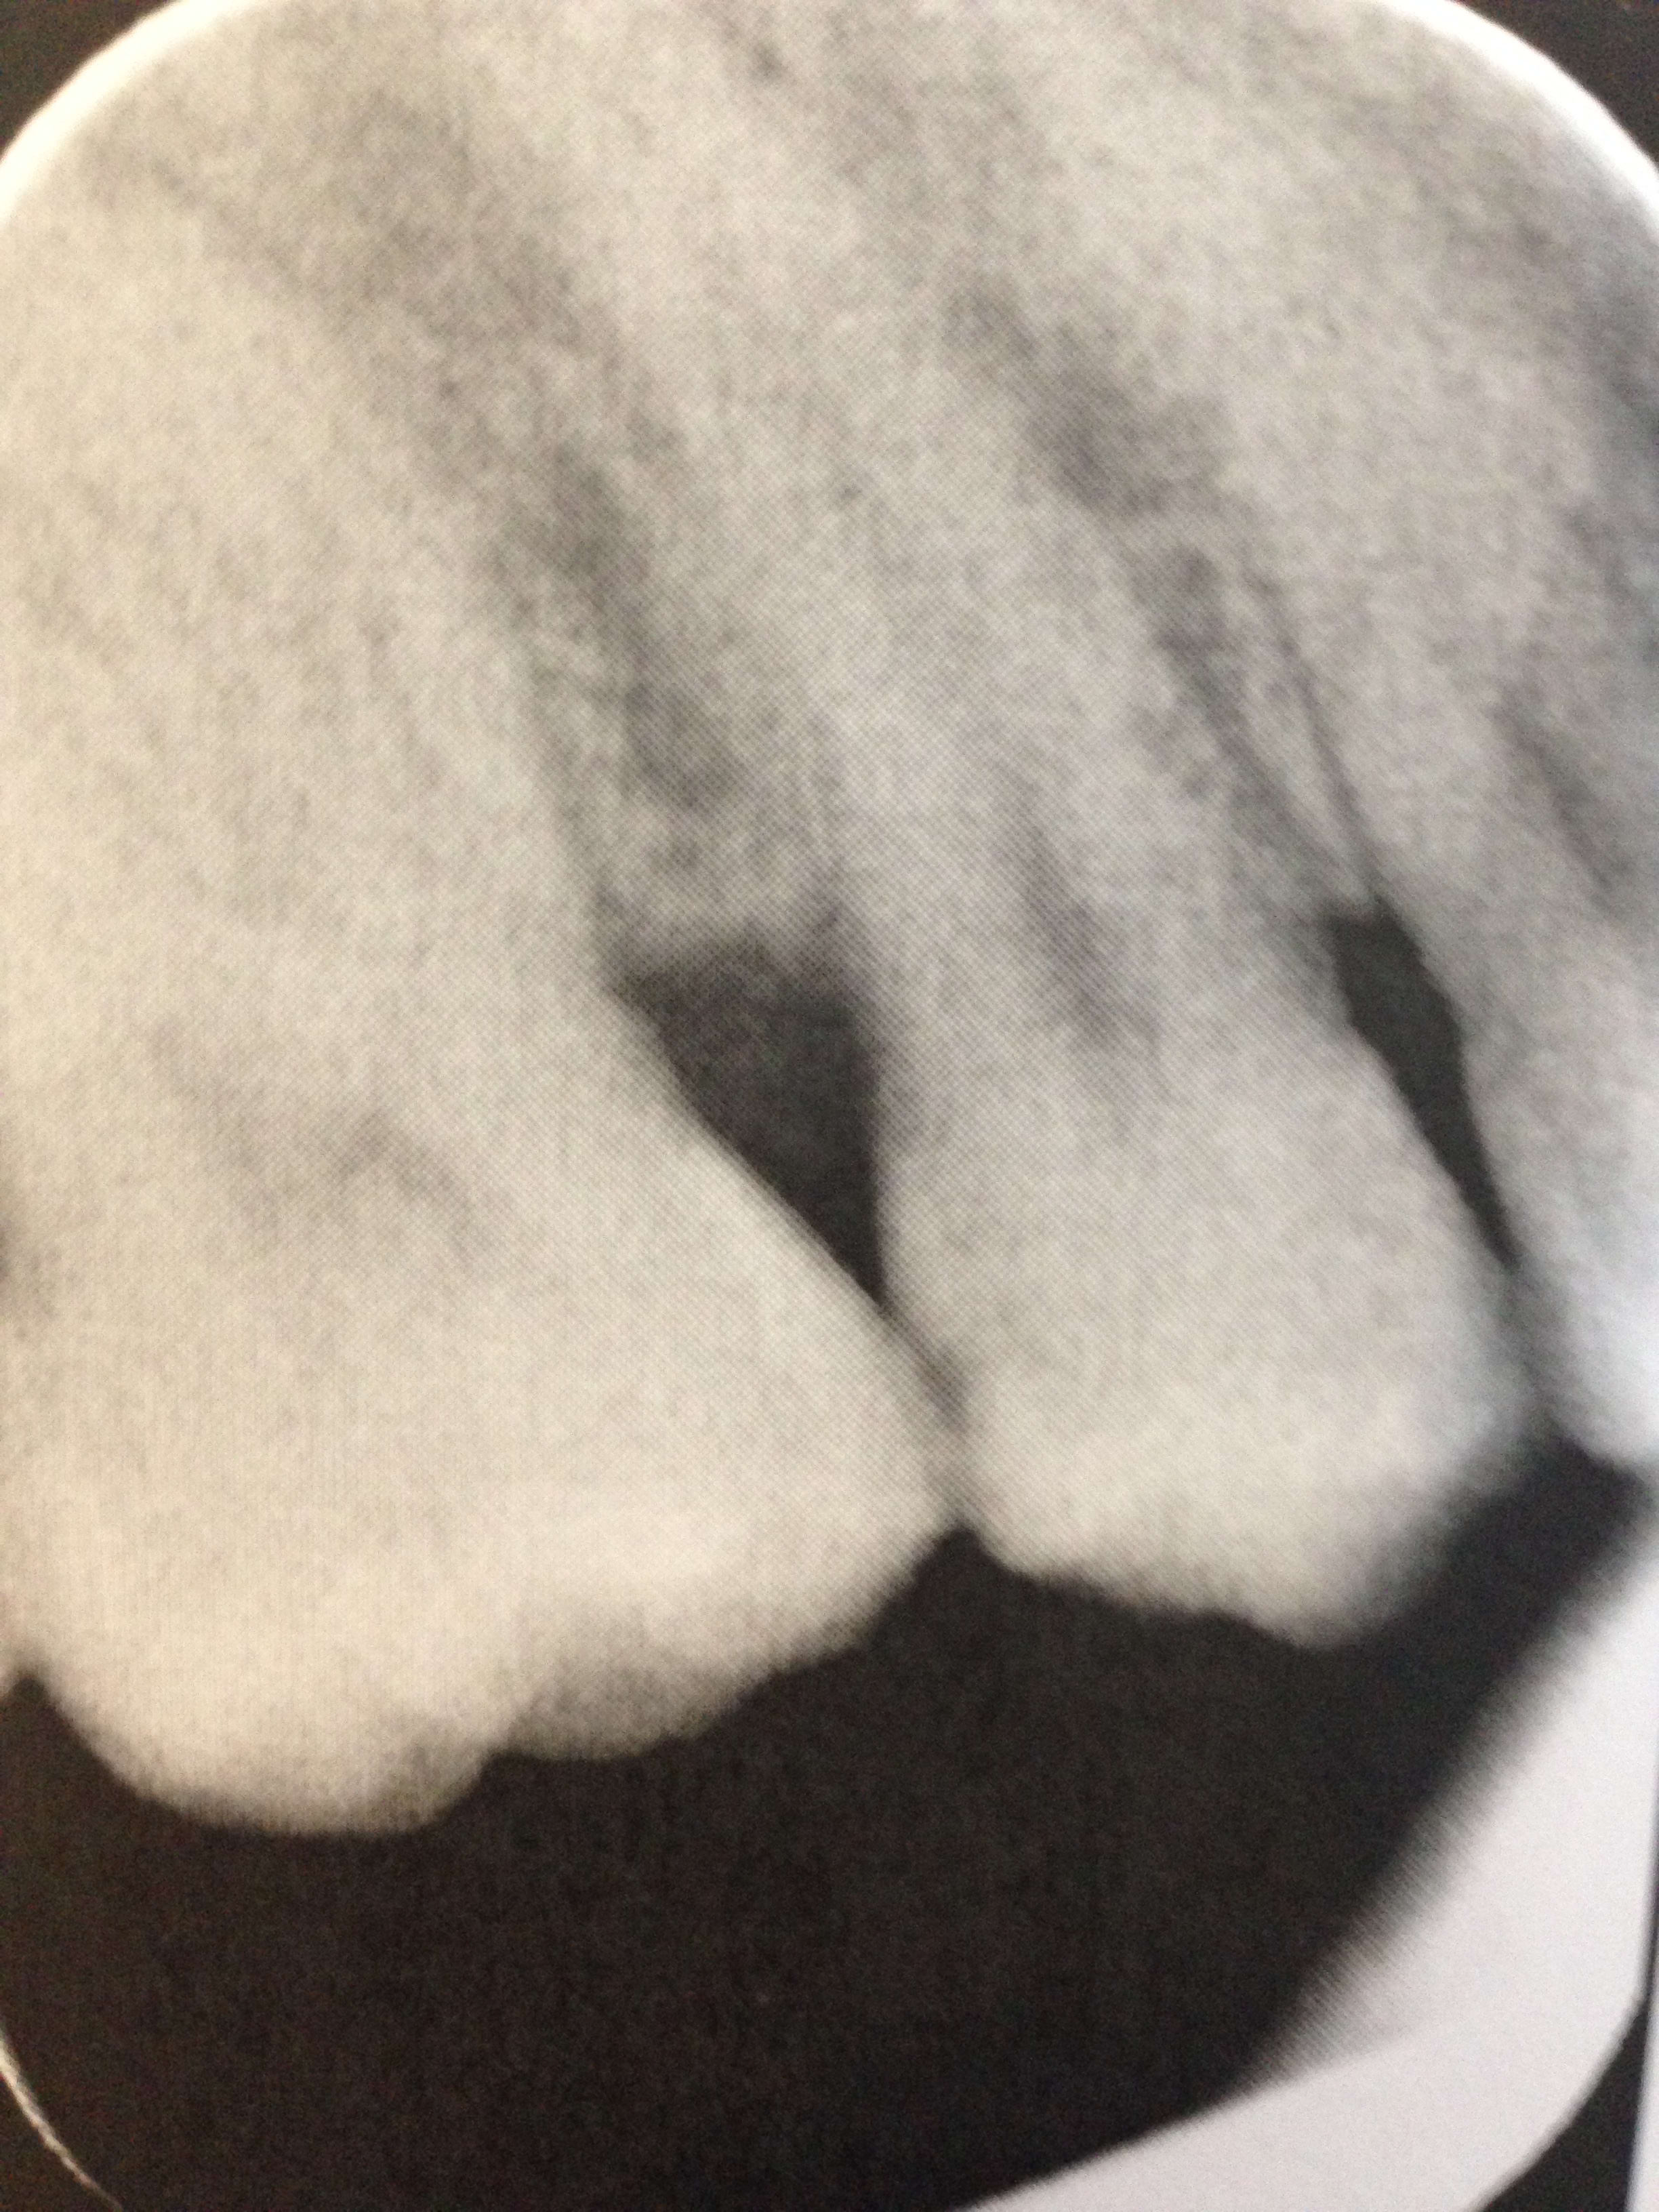

Voilà ce qu'un patient par exemple m'a amené dans mon babinet : des clichés radios d'une 15 réalisés avant et après, actes réalisés dans un centre low cost. Il m'a amené ça hier. Le patient était totalement en panique. Plus du tout confiance en la profession

Photos prises avec mon iphone de ces fameux clichés réalisés dans un centre low cost : le mec lui a laissé une fraise dans la chambre quand même et n'a pas accepté de le reprendre en urgence. Tu m'étonnes qu'on soit mal vu par les patients 😊. Je vous avouerais que je me suis quand même fendu la poire quand j'ai vu ça.

---> j'ai passé 1/2h pour convaincre le patient qu'il fallait dépulper tellement il était en panique et tellement il n'avait plus confiance en la profession